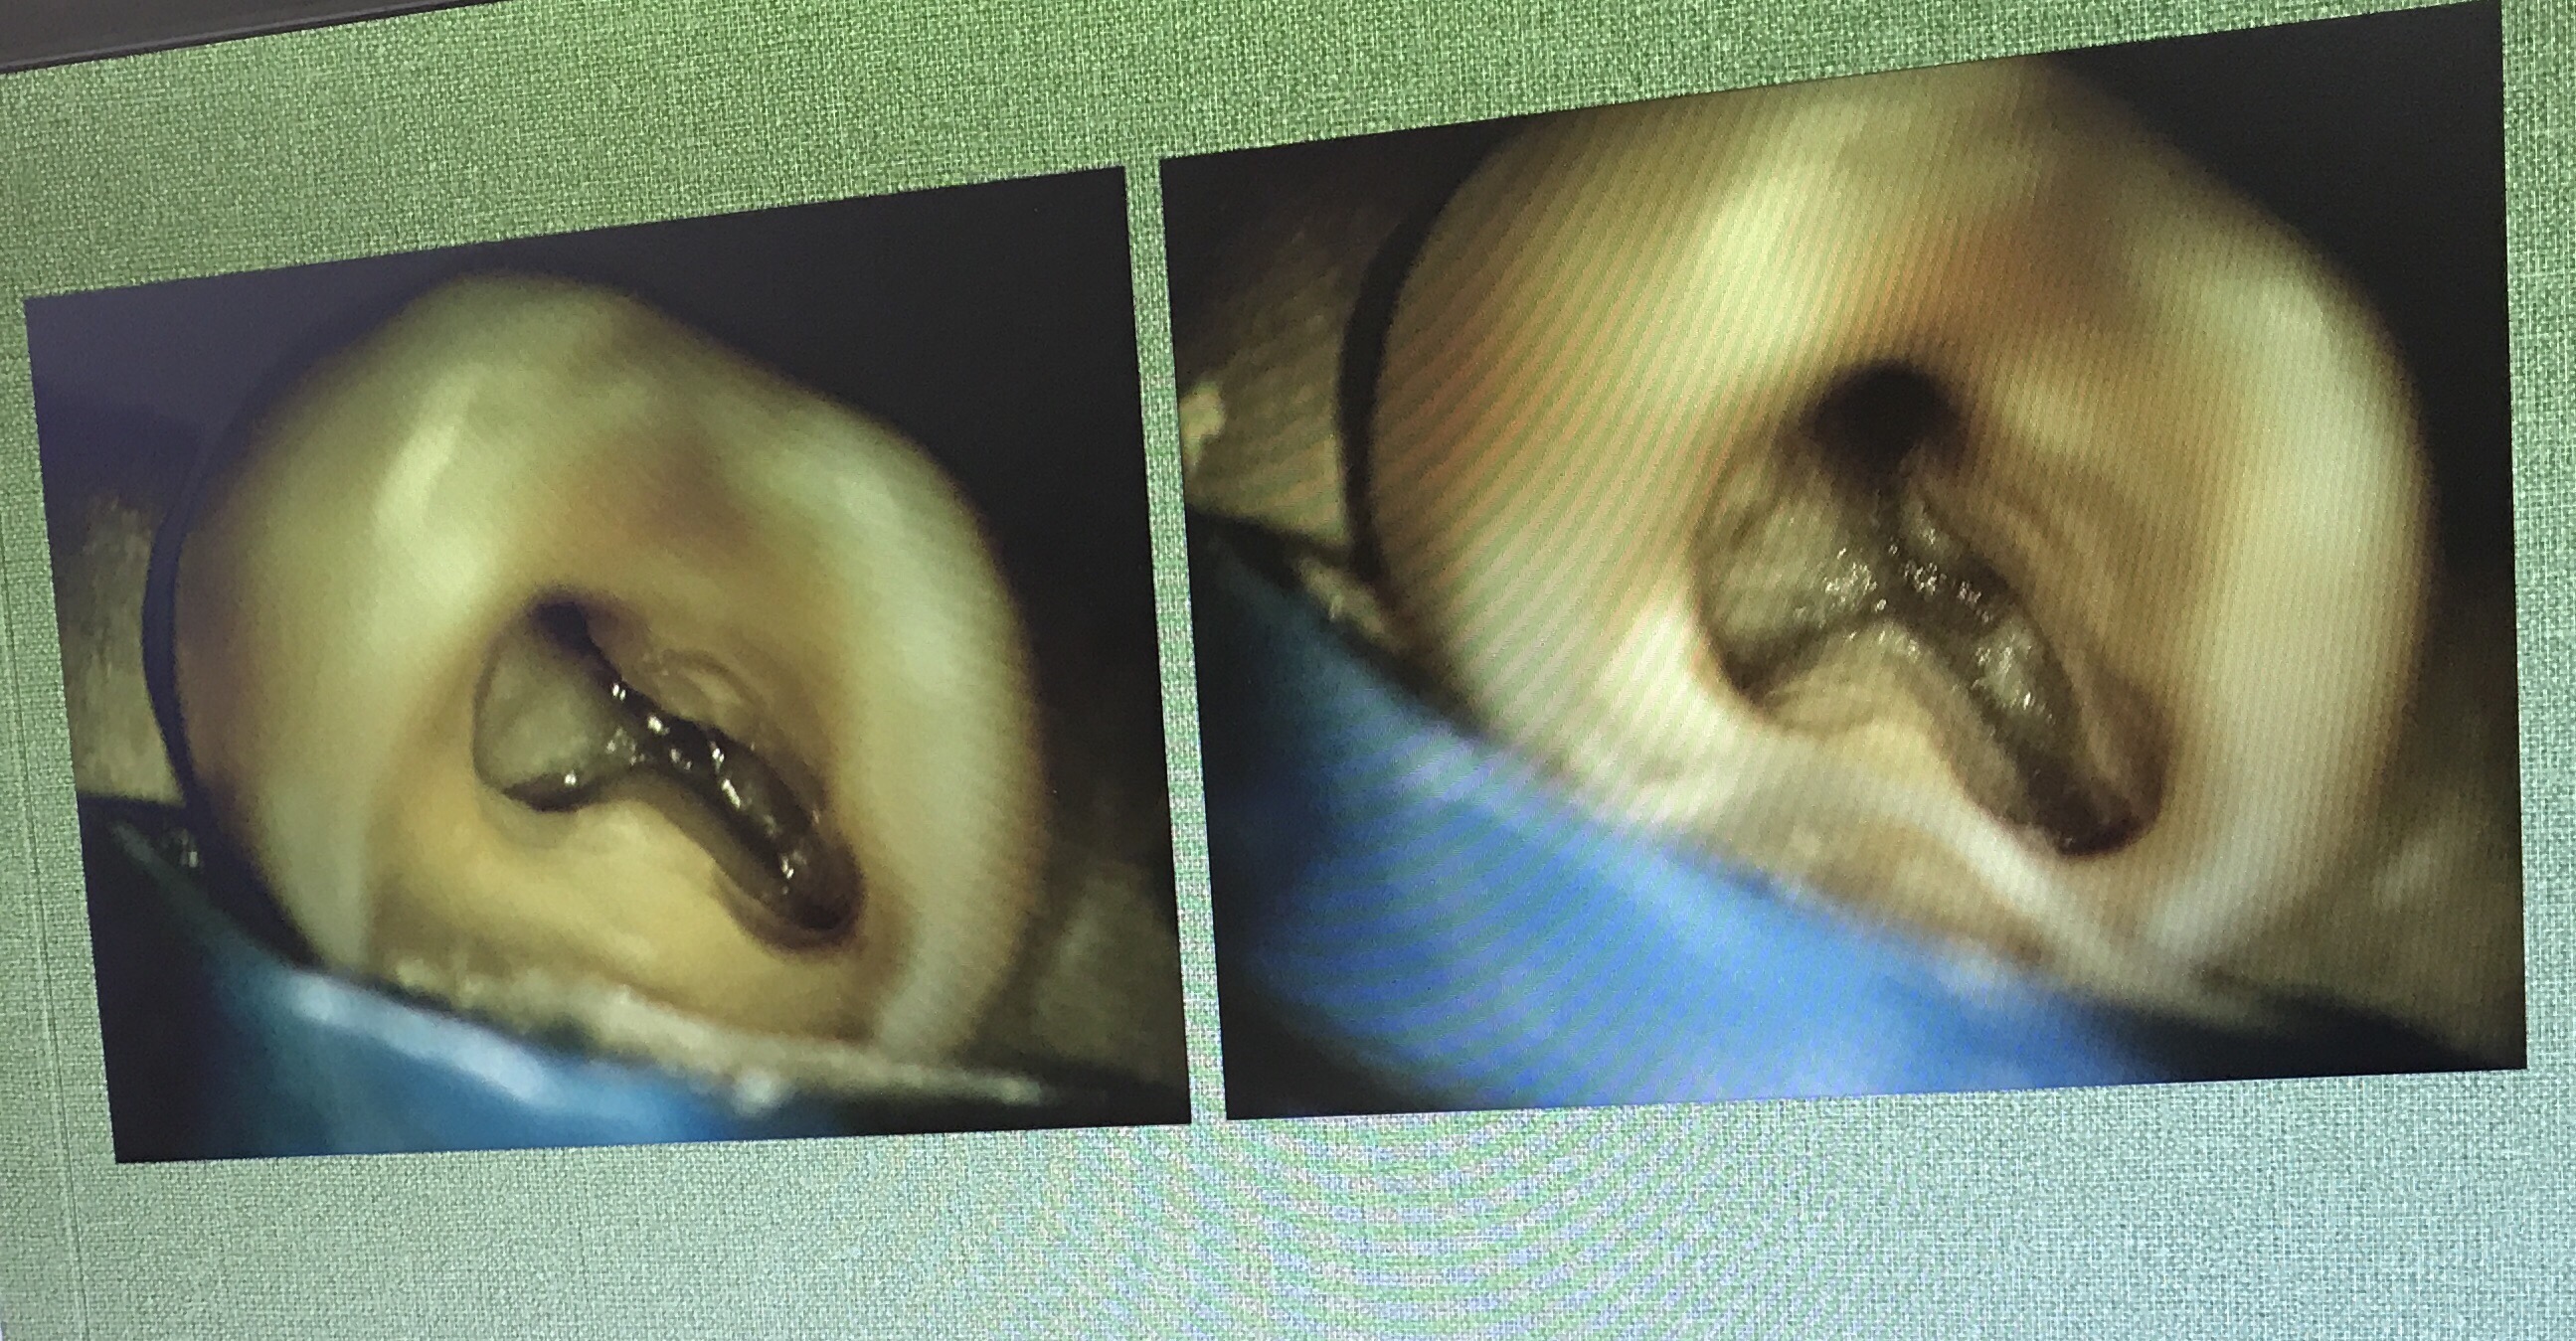

มี VDO demon การใช้งานมาฝากนิดหน่อยครับ แสดงวิธี Locate canal

Lecture ต่อมา คือหลักการซ่อมแซม perforate